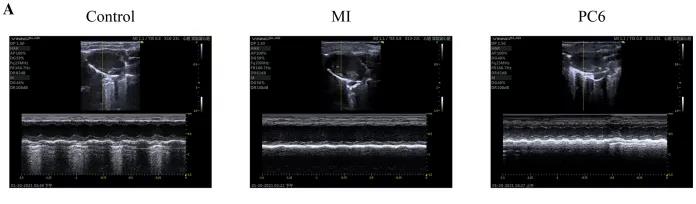

成年雄性C57BL/6雄性小鼠隨機分為對照組、MI組和PC6組。MI組小鼠為通過(guò)結扎冠狀動(dòng)脈左前降支(LAD)形成MI模型,PC6組在造模完成后,針刺內關(guān)穴治療5天后取材。經(jīng)胸超聲心動(dòng)圖評估MI手術(shù)前后小鼠心功能情況,并進(jìn)行血清心肌酶和炎癥細胞因子的測定,之后三組樣本各取3個(gè)重復,共9個(gè)樣本進(jìn)行ONT全長(cháng)轉錄組測序。

為了探討針刺PC6穴對心肌損傷的影響,作者首先評估了心功能和梗死面積。超聲心動(dòng)圖結果顯示MI組的EF(ejection fraction)和FS(fractional shortening)均較對照組明顯降低。PC6穴位治療后,EF和FS均增加。針刺治療5天后, 采用TTC染色檢測梗死面積。結果顯示,針刺治療顯著(zhù)減小心肌損傷的大小。采用ELISA法測定反映急性心肌損傷的心肌特異性血清酶,包括心肌肌鈣蛋白T (cTnT)和心肌肌鈣蛋白I (cTnI)的水平。結果表明,心肌梗死術(shù)后cTnT和cTnI水平升高,針刺可顯著(zhù)降低血清酶水平。